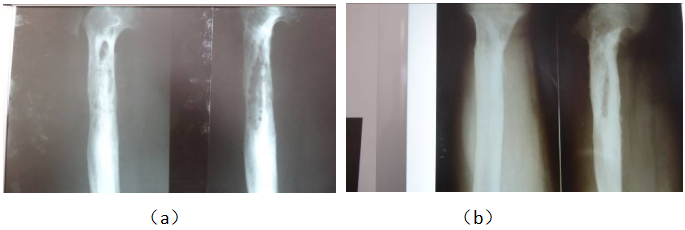

病例2,男,46岁,股骨骨髓炎20年,手术治疗6次。无好转,窦道不愈、流脓水。多个医院告知截肢治疗。治疗7个月后,死骨消失,瘘管愈合,恢复正常工作。治疗前左股骨干95%面积骨髓炎,密度不均匀(a)。治疗后死骨消失,窦道愈合,骨密度均匀(b)

Case 2, male, 36 years old, left femur osteomyelitis for 20 years, has been operated on 6 times in a famous professional hospital. Leakage does not heal, first-class pus, can not work, many hospitals told amputation. After 7 months, the dead bone disappeared, the fistula healed and labor resumed. Before treatment, (a) the density of massive dead bone at the lower end of femur was uneven. (b) After treatment, the dead bone disappeared and the density was even.